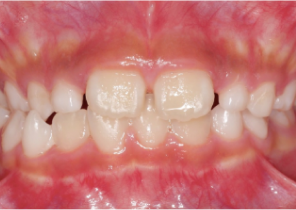

Informe de caso 1

10 años, 0 meses de edad, 18 etapas con dispositivos Invisalign Palatal Expander

Cortesía de la Dra. Sandra Khong Tai

Antes de la disyunción con el sistema Invisalign Palatal Expander

Después de la disyunción con el sistema Invisalign Palatal Expander

Después del tratamiento Invisalign First